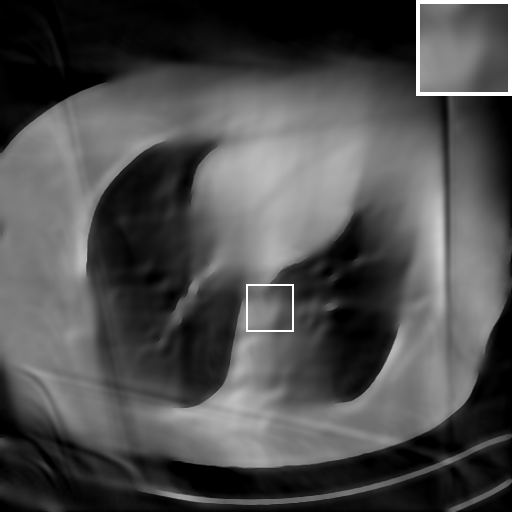

We further increase the noise level contained in the raw data to 10% white Gaussian noises and list the quantitative results in Table IV. It can be observed that the reconstruction performance of the TV model is poor in the case of high-level noises with PSNR dropping by 4 to 5 dB compared to the previous experiments. On the other hand, the performance of the learning-based methods is less sensitive to noises. The SIPID method relying on the sinogram interpolation works better than FBP-Unet. And the deep unrolling methods (i.e., PD-net, IFSR-net, SFSR-net) outperform the traditional iterative algorithm when the scanning range is limited and data is corrupted by noises. Similar to the previous experiments, compared with other deep learning algorithms, our LRIP-nets give the reconstruction results with higher PSNR and SSIM. Moreover, the low-resolution image obtained by the projection data down-sampled with rate 1/8 always gives the best reconstruction results with more than 2 dB PSNR and 0.05 SSIM increments compared to the PD-net. Fig. 6 illustrates the reconstructed images from different methodologies with scanning angular range of and 10% Gaussian noises. It can be seen that the both TV model and the FBP-Unet suffers from significant artifacts, which present distortions in the angular range of the missing scan. Other learning-based methods provides better visual qualities than FBP-Unet, and our LRIP-net1/8 still gives the best reconstruction result with correct boundaries and fine structures.